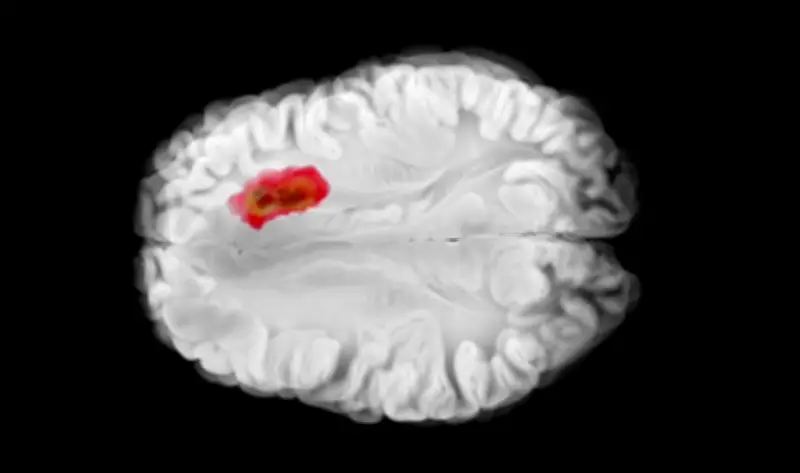

في تطور علمي مثير، كشفت دراسة حديثة نُشرت في مجلة طبية مرموقة عن دور حاسم لفيتامين معين في تعزيز جهاز المناعة البشرية لمحاربة أحد أخطر أنواع سرطان الدماغ، المعروف باسم الورم الدبقي. هذا الاكتشاف قد يفتح آفاقاً جديدة في تطوير علاجات أكثر فعالية لهذا المرض الخبيث.

أجرى فريق من الباحثين في جامعة كبرى دراسة شاملة على مجموعة من المرضى المصابين بسرطان الدماغ، حيث ركزوا على تحليل تأثيرات فيتامين د على جهاز المناعة. وجدت الدراسة أن هذا الفيتامين يعمل على: